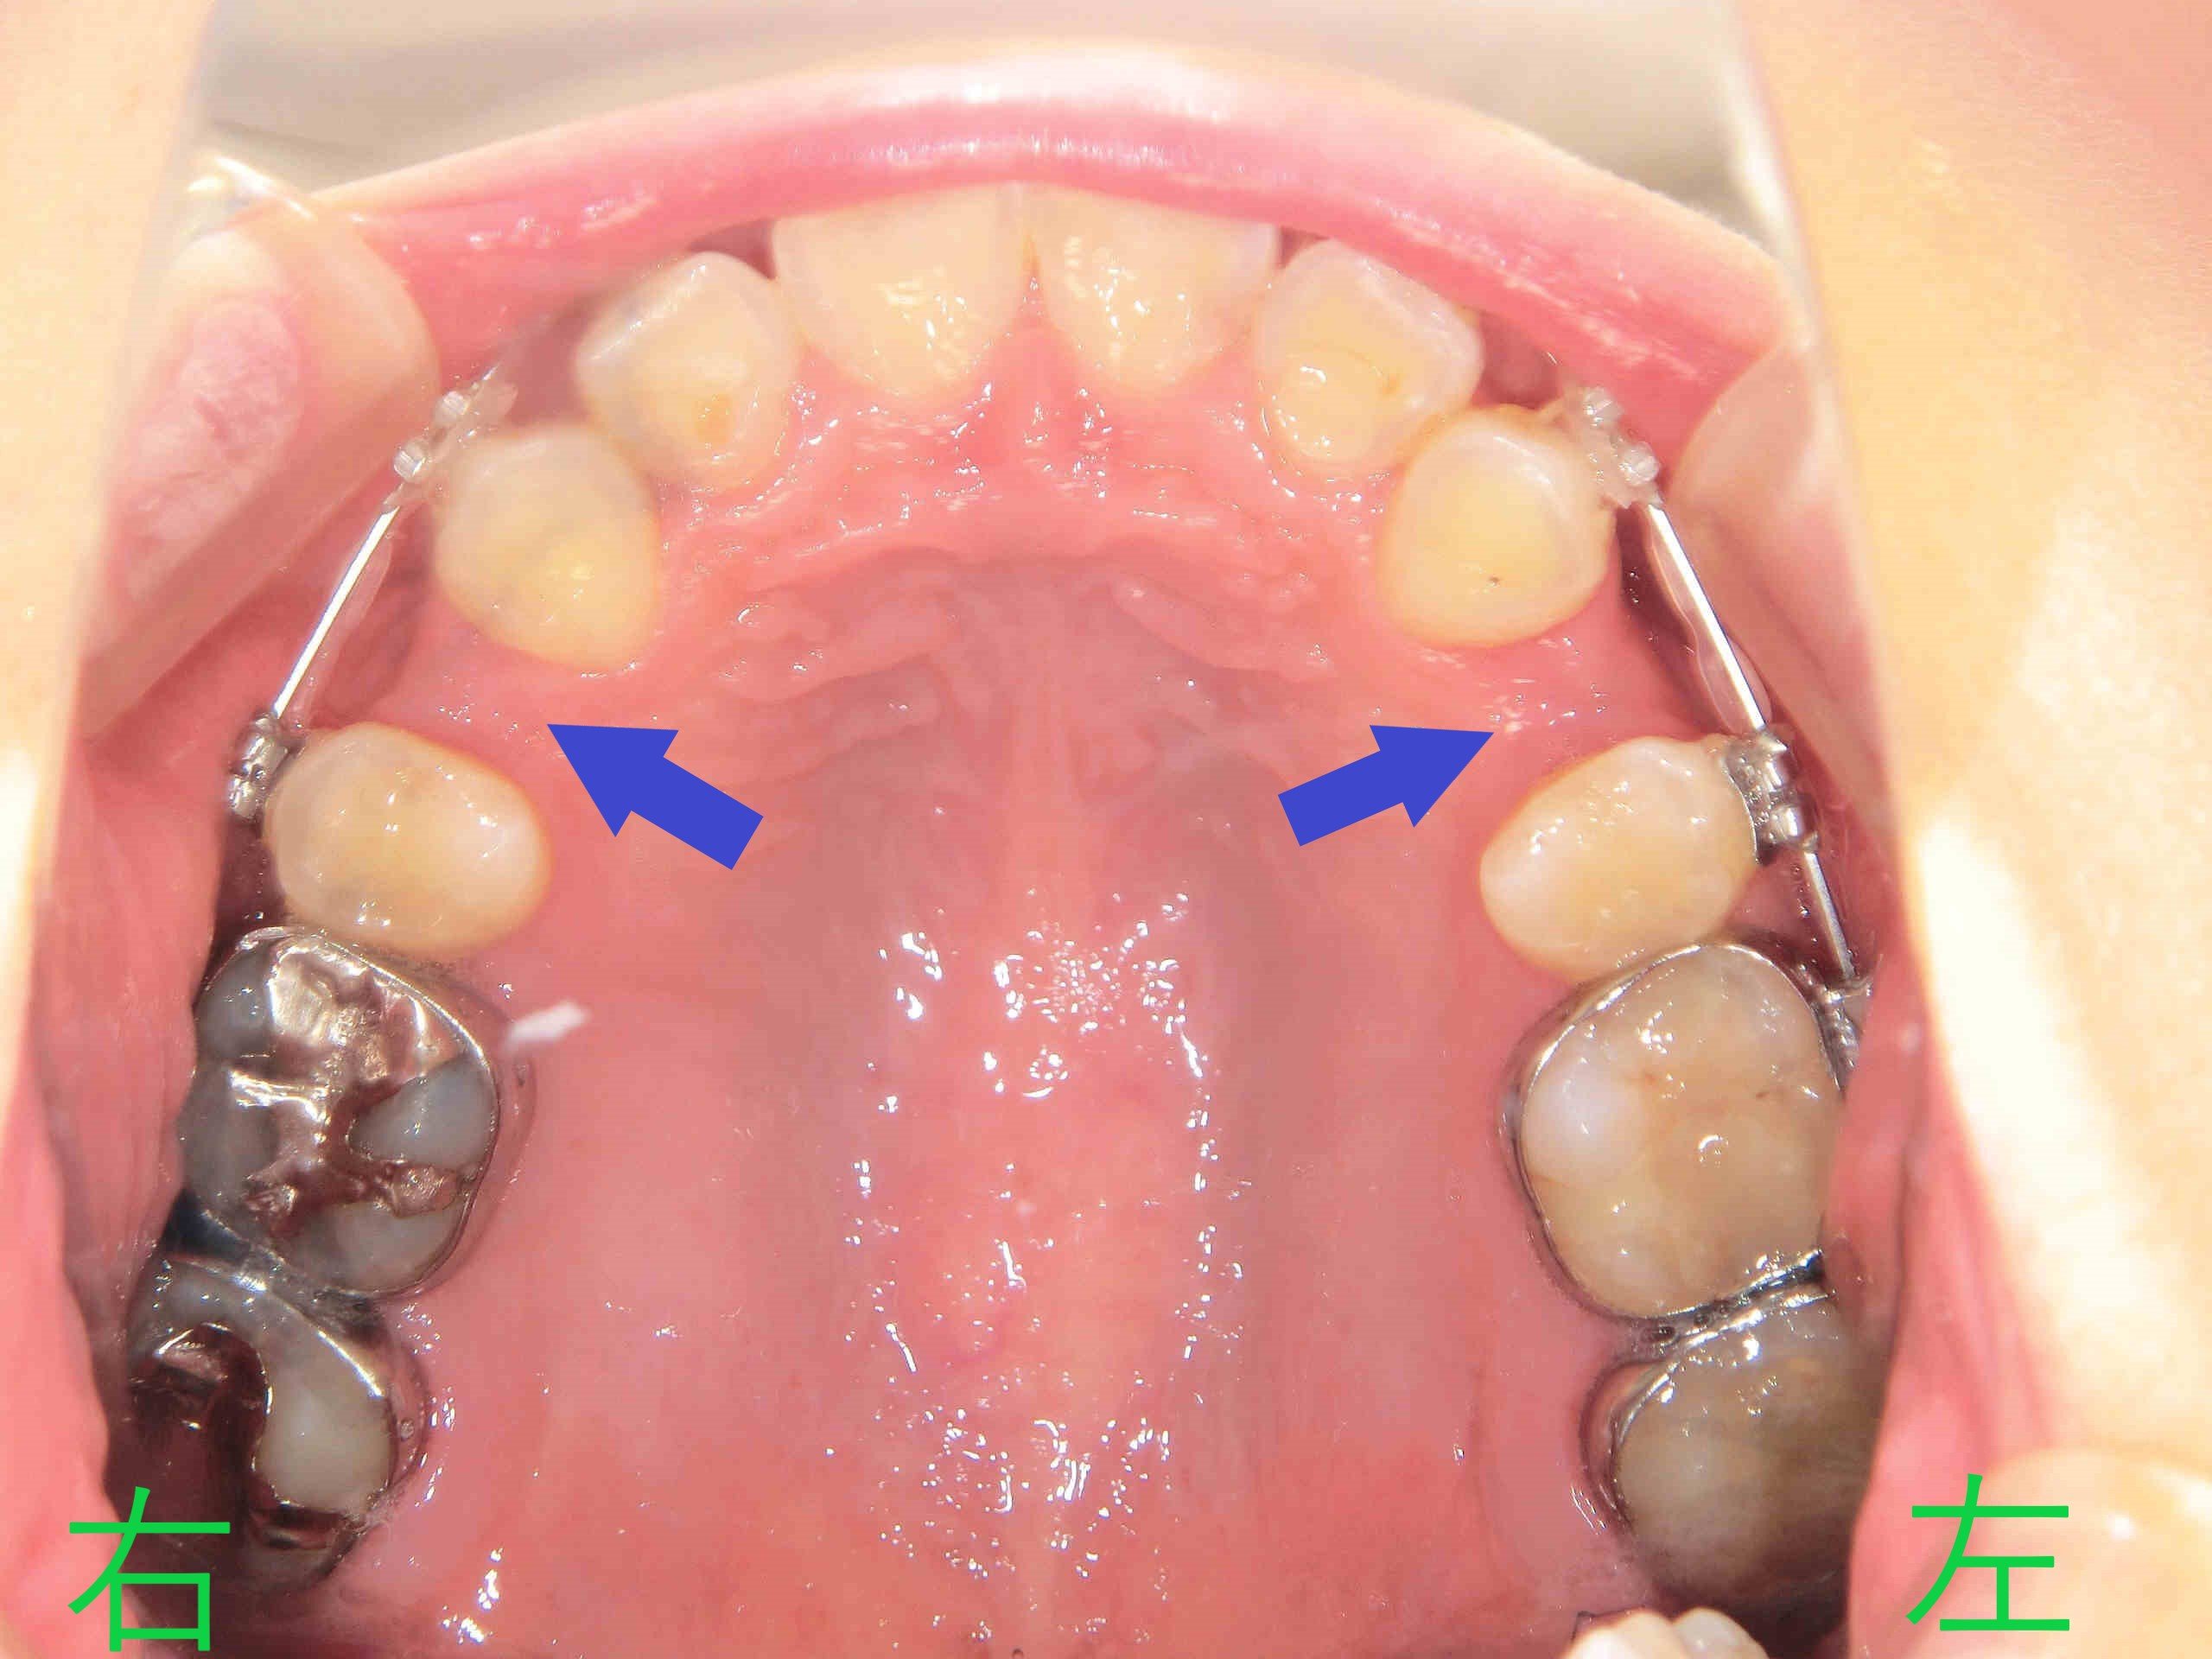

また、上顎を下から撮影した写真(同8か月後)では、抜歯した第一小臼歯のスペースに向けて、犬歯を含む前歯群が後方へ移動している様子が見られます(青色矢印)。

矯正開始から13か月後の写真では、上顎前歯の前突感がさらに軽減されているのが明瞭です(黄色矢印)。また、同時期の上顎歯列の写真(下から見上げたもの)では、抜歯した第一小臼歯のスペースがほぼ閉鎖されている様子が確認できます(青色矢印)。